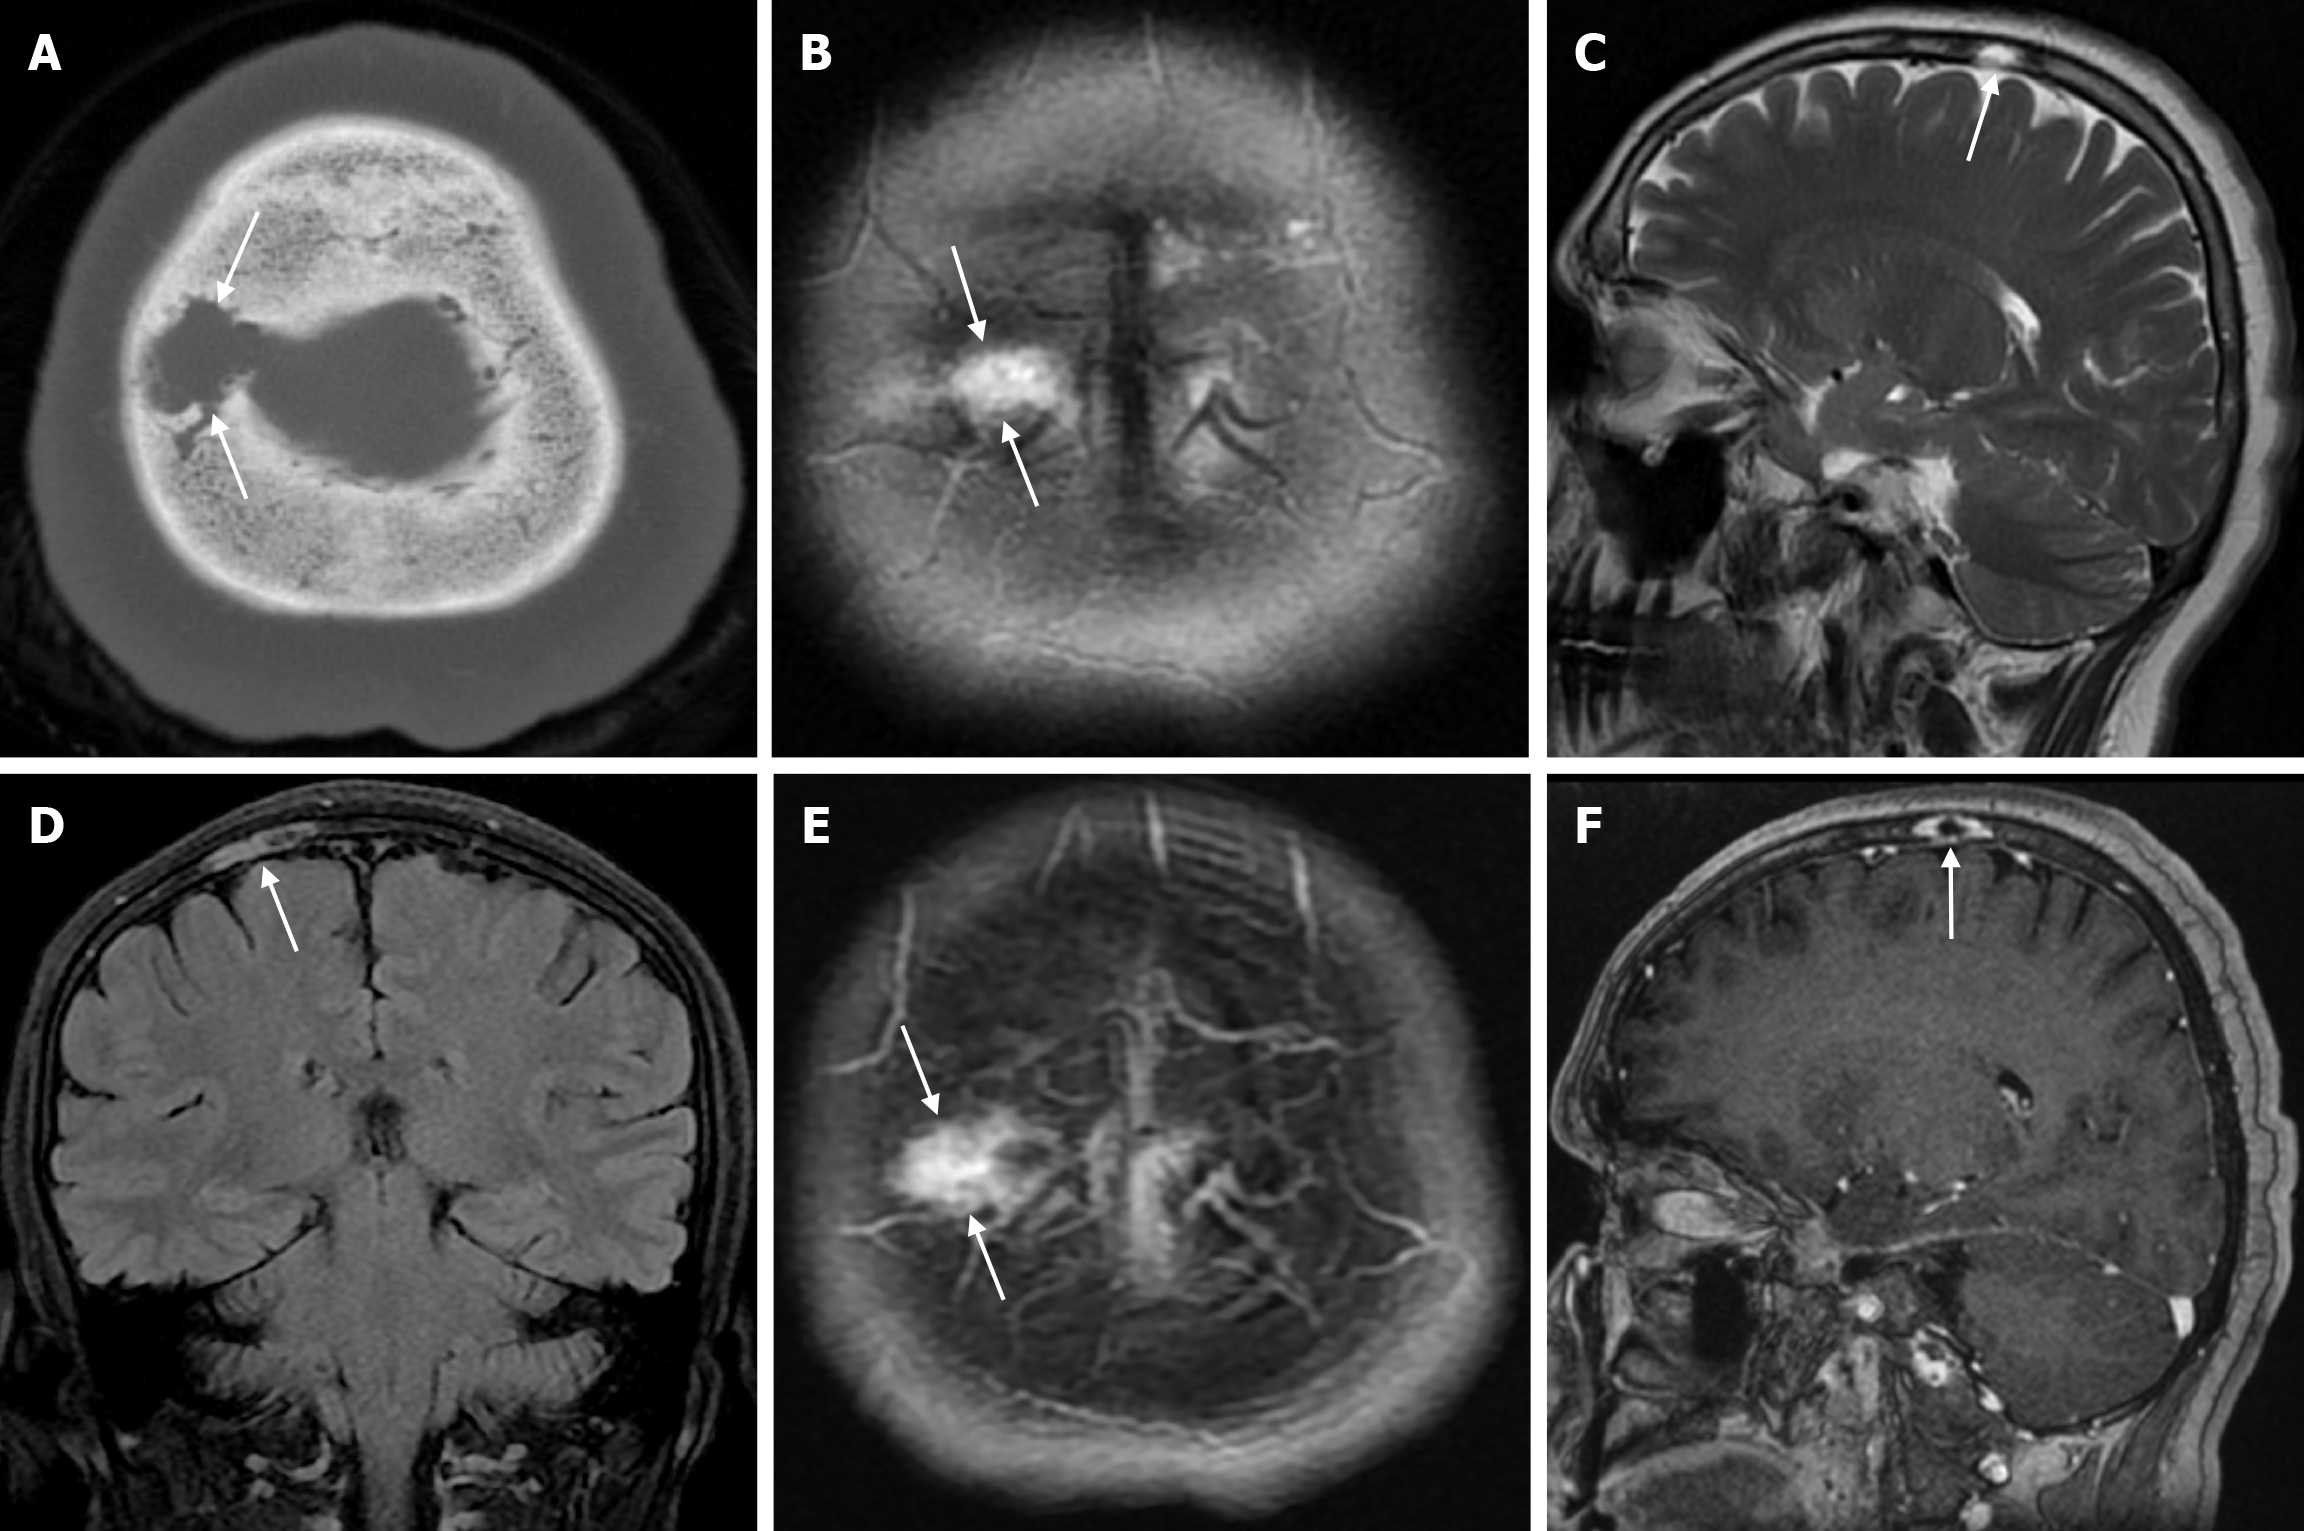

Epidermoid cysts are small or medium-sized, benign, and slow-growing tumors that arise from the remnants of ectodermal cells in the bones of the skull. These cysts can also develop after trauma or surgery. Epidermoid cysts are lined with squamous epithelium. They contain deposits of cholesterol and keratin. These cysts constitute less than 1% of primary intracranial tumours, while intradiploic epidermoid cysts account for less than 0.25% of intracranial tumours. These tumors can occur at any age from the first decade of life to the seventh decade, with a mean age of 32-38 years, and there is no gender predilection. Epidermoid cysts are most commonly found in the frontal, parietal and occipital regions and often involve more than one bone. Epidermoid cysts appear on plain radiography as round or lobulated lytic areas with smooth and sclerotic margins. On CT they appear as non-contrast enhanced intradiploic lytic hypodense lesions with smooth sclerotic borders. Epidermoid cysts often cause remodeling and widening of the inner and outer tables. Epidermoid cysts that appear hyperdense on CT due to bleeding, calcification or high protein content are called white epidermoids and are observed quite rarely. On MRI, epidermoid cysts appear isointense/hyperintense on T2-weighted and fluid-attenuated inversion recovery (FLAIR) images and slightly hyperintense on T1-weighted images (Figure 4). These lesions restrict diffusion on diffusion-weighted imaging but show no contrast enhancement on contrast enhanced sequences[19].

Leptomeningeal cysts can develop as a rare complication of linear skull fractures in children. The incidence is reported in the literature to be between 0.05% and 0.1%. They are usually seen in children under the age of 3. These cysts most commonly occur in the cranial convexity but can also be seen in the posterior fossa and orbital roof. This complication develops as a result of dural tear associated with skull fracture. Laceration of the dura mater leads to herniation of the leptomeninges and filling with CSF. The continuous pulsatile pressure of the CSF and the expansion of the cyst cause resorption of the adjacent bone, erosion of the bone edges and expansion of the skull fracture. The fracture site, together with the thickness of the soft tissues, can be seen on plain radiography. While bone fractures can be better demonstrated with CT imaging, MRI is more useful in distinguishing leptomeningeal cysts from other pathologies. Leptomeningeal cysts are isointense with cerebrospinal fluid on both T1-weighted and T2-weighted images (Figure 10). Associated pathologies such as subdural fluid collections, hematomas, encephalomalacia, and ventricular dilatation may also be seen on CT imaging and MRI. Early diagnosis is important because of the risk of neurological deterioration and seizures, and treatment includes dural repair and cranioplasty[35].